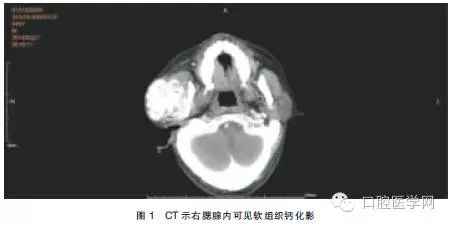

查體:患者面形左右不對稱,右耳前有一約5.0 cm×5.0 cm大小的軟組織隆起,質(zhì)地較硬,與周圍組織界限不清,無活動度,開口度未受影響。血鈣:2.7mmol/L,血磷:2.9mmol/L,肌酐:953μmol/L,尿素氮:5.7mmol/L。使用GE VCT64排螺旋CT進(jìn)行掃描(球管電流:250mA,掃描電壓:120kV,周期:0.4s/周,層厚:5mm),掃描范圍:顱底至頸根部。結(jié)果示:右腮腺區(qū)見團(tuán)塊狀混雜密度(軟組織內(nèi)伴鈣化)影,邊界欠清,與腮腺組織及血管分界不清,與咬肌及周圍骨結(jié)構(gòu)分界欠清(圖1)。